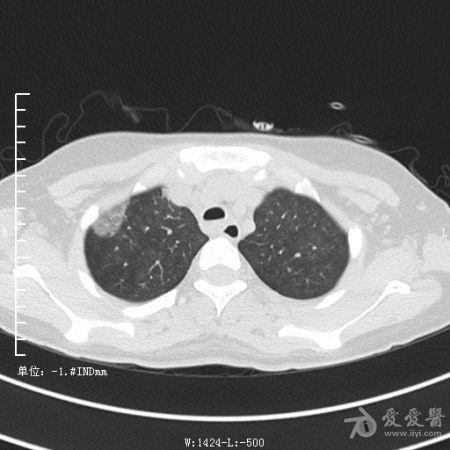

典型支气管扩张及肺水肿CT片

典型支气管扩张肺水肿